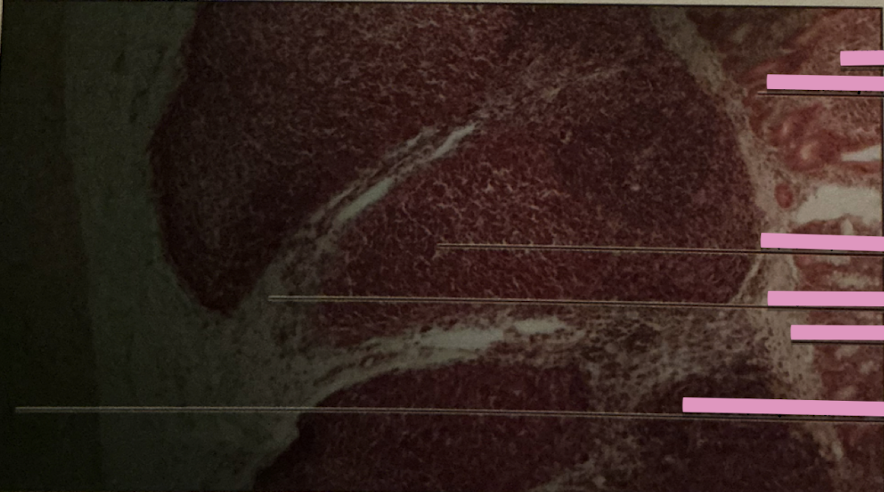

thymus

thymus

where does development of T cells occur?

Hassall’s Corpuscle

___________ sites accumulate dead T cells & involved in development of reg. T cells